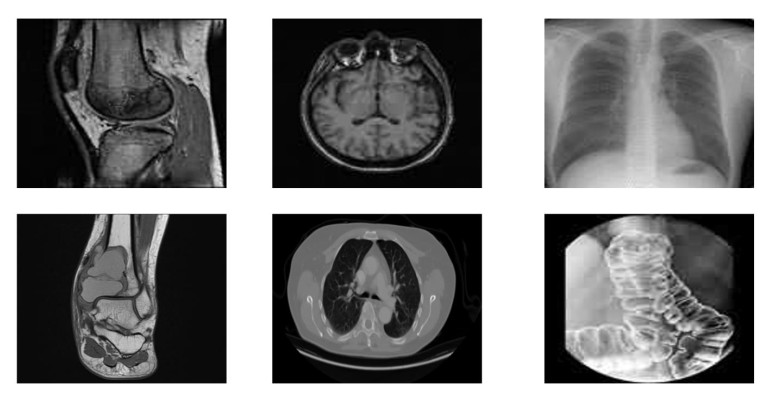

• Safeguarding medical images against unauthorized access and alteration during storage and transmission is a critical challenge in modern telemedicine systems. This paper introduces a robust method to encrypt medical images in which the confusion stage is driven by a four-dimensional (4D) fractional-order chaotic system, and the diffusion process utilizes a symmetric matrix integrated with a one-dimensional (1D) chaotic map. The fractional 4D chaotic system reveals intricate dynamic behavior and is extremely sensitive to initial conditions, which enhances the confusion capability by thoroughly scrambling pixel positions. The symmetry matrix is combined with a generated chaotic sequence from a 1D chaotic map during the diffusion process that ensures strong pixel intensity diffusion and key dependence. Numerous experiments carried out on a variety of medical images confirm the outstanding performance of the suggested method. The suggested method features a key space exceeding 2100, exhibiting significant robustness to brute-force attacks. It achieves unified average changing intensity (UACI) values above 33% and number of pixels change rate (NPCR) values exceeding 99.6%, confirms robustness to differential attacks, and successfully resists chosen-plaintext and known-plaintext attacks. Additionally, the low pixel correlation and uniform histograms, along with average values of information entropy of 7.9973 and 7.9993 for 256×256 and 512×512 images, respectively, demonstrate strong resilience to statistical attacks. Furthermore, robust evaluations against cropping and noise attacks demonstrate the scheme's practical security, highlighting its suitability for the safe storage and transmission of medical images in healthcare applications. Compared with related methods, the suggested method offers superior security performance.